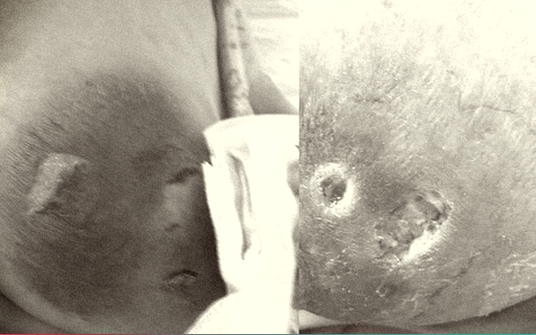

Kết quả khám lâm sàng cho thấy: Phần ngực của sản phụ có một ổ nhiễm khuẩn, chảy mủ... Qua hội chẩn chuyên khoa, các bác sĩ chẩn đoán: Sản phụ bị áp xe vú, ngực chảy mủ do tắc tuyến sữa và chỉ định chích áp xe và làm vật lý trị liệu.

Khi tạo áp xe, người nhà của bệnh nhân lại nặn bóp quá sớm làm ổ nhiễm trùng lan rộng gây tổn thương tổ chức mềm lành xung quanh, khiến bệnh lý nặng hơn.